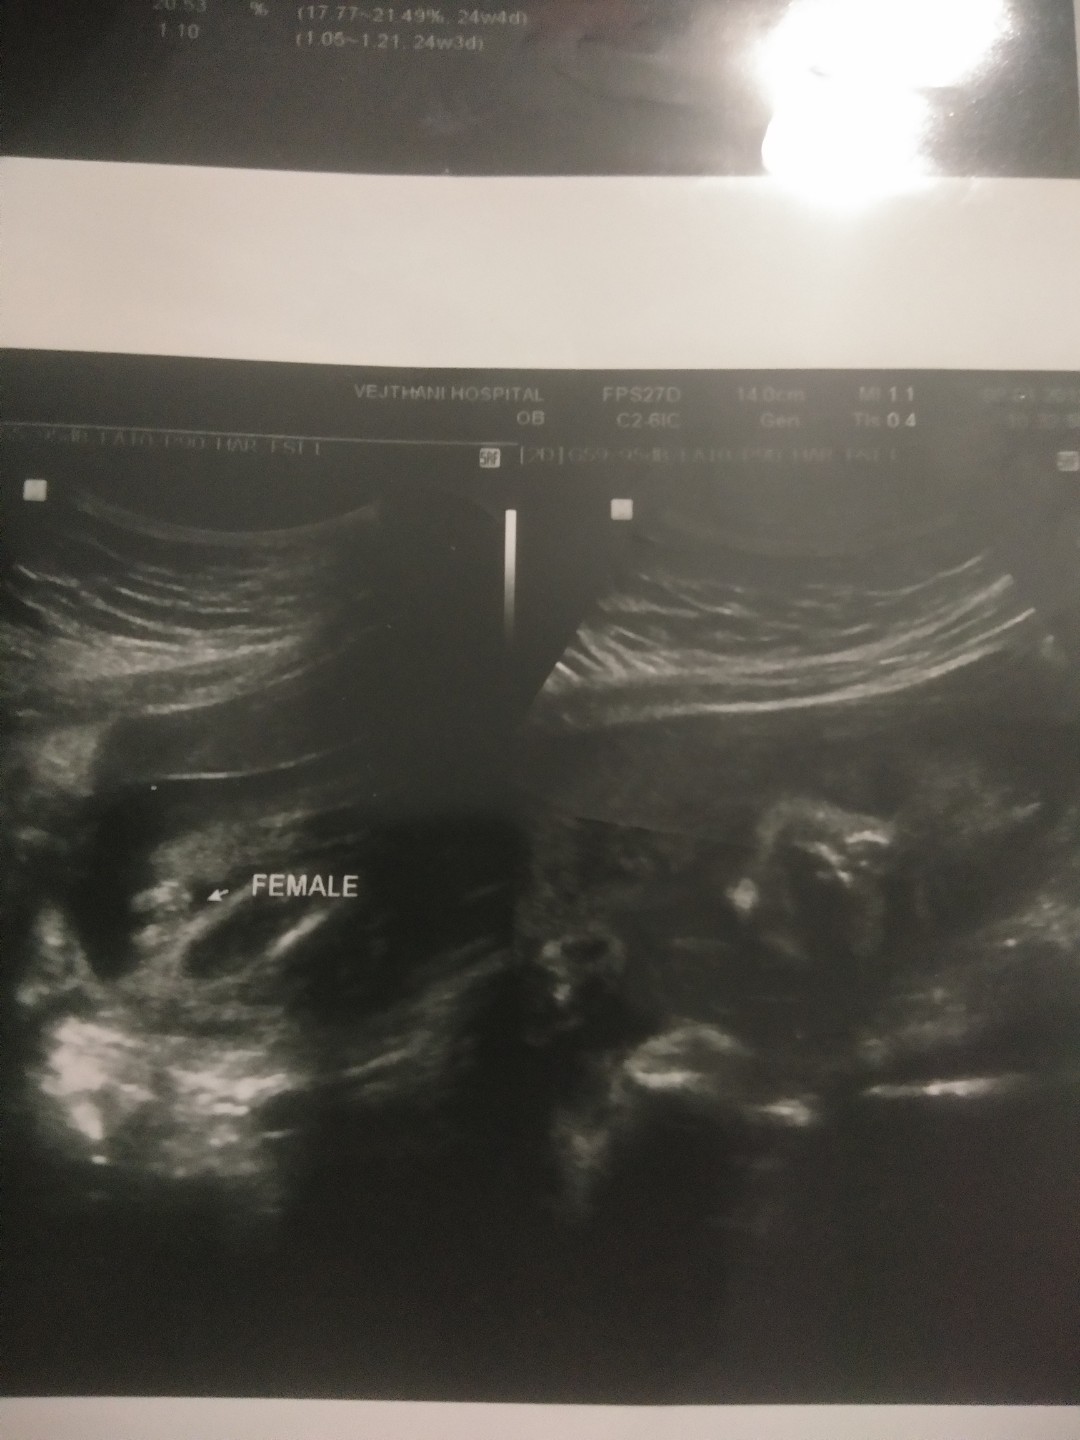

ของลูกสาวค่ะ ตอน6เดือน

หมอว่าผญ. ค่า ตอน20w

ลูกสาวจ้า 20w

ลูกสาวค่ะ